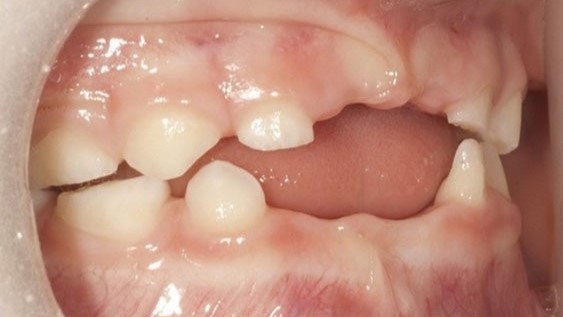

Dạng Odontohypophosphatasia được đặc trưng bởi tình trạng rụng răng sữa sớm dù đã có chân răng hoàn chỉnh và/hoặc sâu răng nghiêm trọng. X-quang xương hàm cho thấy xương ổ răng bị tiêu giảm, buồng tủy to và ống tủy mở rộng.

Trẻ mắc bệnh HPP thường gặp tình trạng răng rụng sớm bất thường, đặc biệt là răng sữa. Răng thường yếu, men răng dễ bị tổn thương, và lợi không đủ chắc chắn để giữ răng. Tình trạng này không chỉ ảnh hưởng đến thẩm mỹ mà còn gây khó khăn trong việc nhai và phát âm.